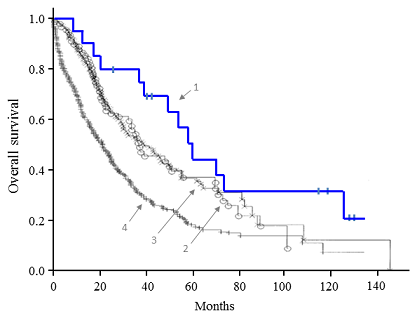

非小細胞肺がんの脳転移における全脳照射の意義は がん情報サイト

Https Hosp Gifu U Ac Jp Center Gan Img 30 Cb01 Pdf

Https Hosp Gifu U Ac Jp Center Gan Img 30 Cb01 Pdf